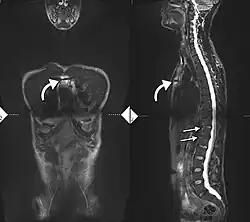

If these criteria still do not give a compelling diagnosis magnetic resonance imaging (MRI) may be useful.[22][24] MRI can show inflammation of the sacroiliac joint.

Options for earlier diagnosis are tomography and MRI of the sacroiliac joints, but the reliability of these tests is still unclear.

T1-weighted MRI with fat suppression after administration of gadolinium contrast showing sacroiliitis in a person with ankylosing spondylitis